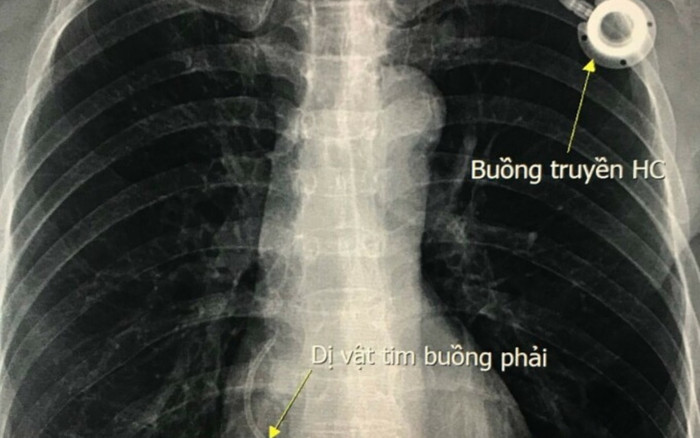

Theo đó, ngày 11/11, Bệnh viện Hữu nghị Việt Đức tiếp nhận trường hợp người bệnh N.T.H (54 tuổi) ở Kim Bôi, Hòa Bình nhập viện do có dị vật mắc kẹt ở tim.

Dị vật được phát hiện ở buồng tim. (Ảnh: BSCC).

Đến tháng 11/2021, sau 6 năm, dây nối của buồng truyền bị đứt và trôi theo mạch máu và bị kẹt lại ở trong tim. Tại Bệnh viện Hữu nghị Việt Đức, người bệnh được thăm khám kĩ lưỡng, và tiến hành can thiệp lấy dị vật, cũng như buồng truyền dưới da.

ThS.BS Thân Văn Sỹ, Khoa Chẩn đoán Hình ảnh, Bệnh viện Hữu nghị Việt Đức cho biết, các bác sĩ đã sử dụng dụng cụ can thiệp đưa vào buồng tim và lấy dị vật ra ngoài chỉ trong vài phút.